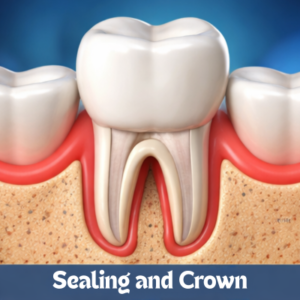

ROOT CANAL

ROOT CANAL

ROOT CANAL

ROOT CANAL

CROWNS AND BRIDGES

CROWNS AND BRIDGES

CROWNS AND BRIDGES

CROWNS AND BRIDGES